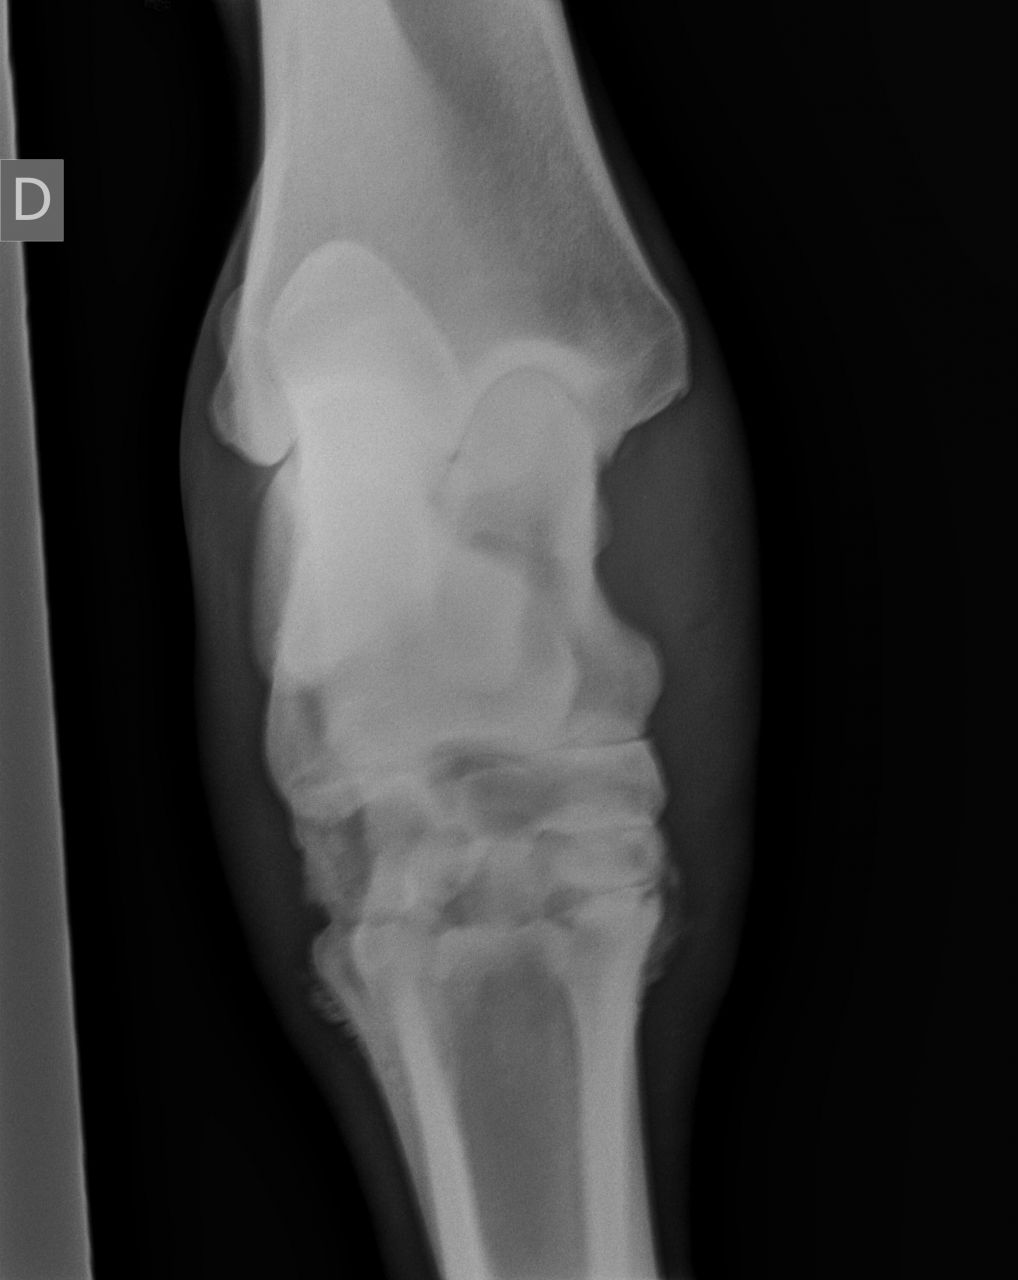

| Dire merci | Voici une radio prise en octobre 2010, [url=https://www.1cheval.com/membre/services/photos/images/191702.jpg" class='zoombox zgallery3279789' ] ![]() et une en décembre : [url=https://www.1cheval.com/membre/services/photos/images/191703.jpg" class='zoombox zgallery3279789' ] ![]() comme tu vois, c'était pas joli joli ! |

| Dire merci | Voici 2 autres clichés encore plus parlant : en octobre : [url=https://www.1cheval.com/membre/services/photos/images/191705.jpg" class='zoombox zgallery3279806' ] ![]() en décembre : [url=https://www.1cheval.com/membre/services/photos/images/191706.jpg" class='zoombox zgallery3279806' ] ![]() oh, tu sais, aujourd'hui, j'en parle s'en soucis et en étant contente du résultat, mais au moment où, je suis passé par des questionnements et des remises en cause pas possible, est ce que je fais bien, est ce que j'ai raison, ne devrais-je pas écouter les autres et ne pas m'acharner, etc...? sauf que les autres, ils ne sont pas à ta place, alors, j'ai écouté mon instinct. financièrement, j'y ai laissé des plumes, heureusement, les dépenses étaient étalées car dur avec un smic. Et pis, ben une fois qu'on a commencé, on va jusqu'au bout, pas possible à mi-parcourt d'arrêter, vaut mieux alors ne pas commencer. Je comprends par quoi tu passes. La fêlure de ton cheval n'est pas si grave que ca. Evidemment, c'est un mot impressionnant, surtout qu'on associe facilement chez le cheval fracture= fichu. Qu'est il envisagé comme soins pour ton cheval? Qui est-il? A quoi est-il destiné? |